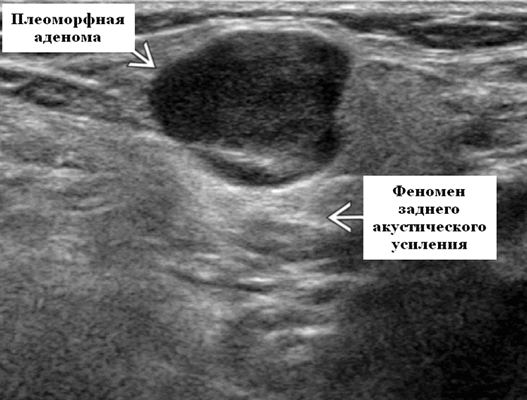

- Четко выраженная, плотная и гипоэхогенная опухоль на УЗИ по сравнению с прилегающей тканью слюнной железы.

- Однородная внутренняя эхо-структура с задним акустическим усилением

Общие особенности при ультразвуковом исследовании. Лучший диагностический признак: четко очерченная внутрижелезистая опухоль ПЧЖ, которая может выступать на ножке от края железы в поднижнечелюстное пространство (ПЧП), когда она становиться большой

Серошкальное УЗИ. Хорошо выраженная, солидная и гипоэхогенная по сравнению с прилегающей тканью слюны. Однородная внутренняя эхо-структура с задним акустическим усилением. Опухоль имеет несколько тканевых границ и позволяет звуку легко проникать, вызывая улучшение заднего отдела. Большие опухоли могут иметь неоднородные внутренние эхосигналы из-за кровоизлияния и некроза. Гетерогенная плеоморфная аденома может иметь нечеткие границы, имитирующие злокачественную опухоль. Большие опухоли могут иметь дольки и появляться на ножке. Необычный кальциноз при ультразвуковом сканировании наблюдается при давней опухоли. Кожа и подкожные ткани в норме